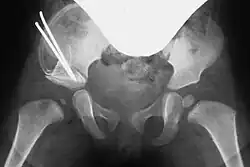

Acetabuloplasty, Step 1: Osteotomy of the ilium -

Acetabuloplasty, Step 2: Tilting the acetabular fragment downward -

Acetabuloplasty, Step 3: Insertion of the bone wedge -

Acetabuloplasty, Step 4: Optional fixation with a Kirschner wire

All osteotomy techniques require only a small incision between the groin fold and iliac crest. The muscles are bluntly separated to expose the ilium. The periosteum is detached just above the acetabulum, and the iliac bone is laid bare.[4]

Pemberton osteotomy

In the Pemberton technique, under continuous X-ray guidance, the ilium is notched approximately 5 mm above the acetabular rim using a flat chisel, and the osteotomy is extended toward the Y-shaped physis. The acetabular fragment is then tilted downward and forward under X-ray control to achieve anatomical reconstruction.[7][10]

In both techniques, a suitably shaped bone wedge is inserted into the resulting gap under X-ray guidance. If needed, the wedge can be fixed with an osteosynthesis wire (Kirschner wire). The procedure typically takes 45 to 60 minutes for an experienced surgeon.[3][11]